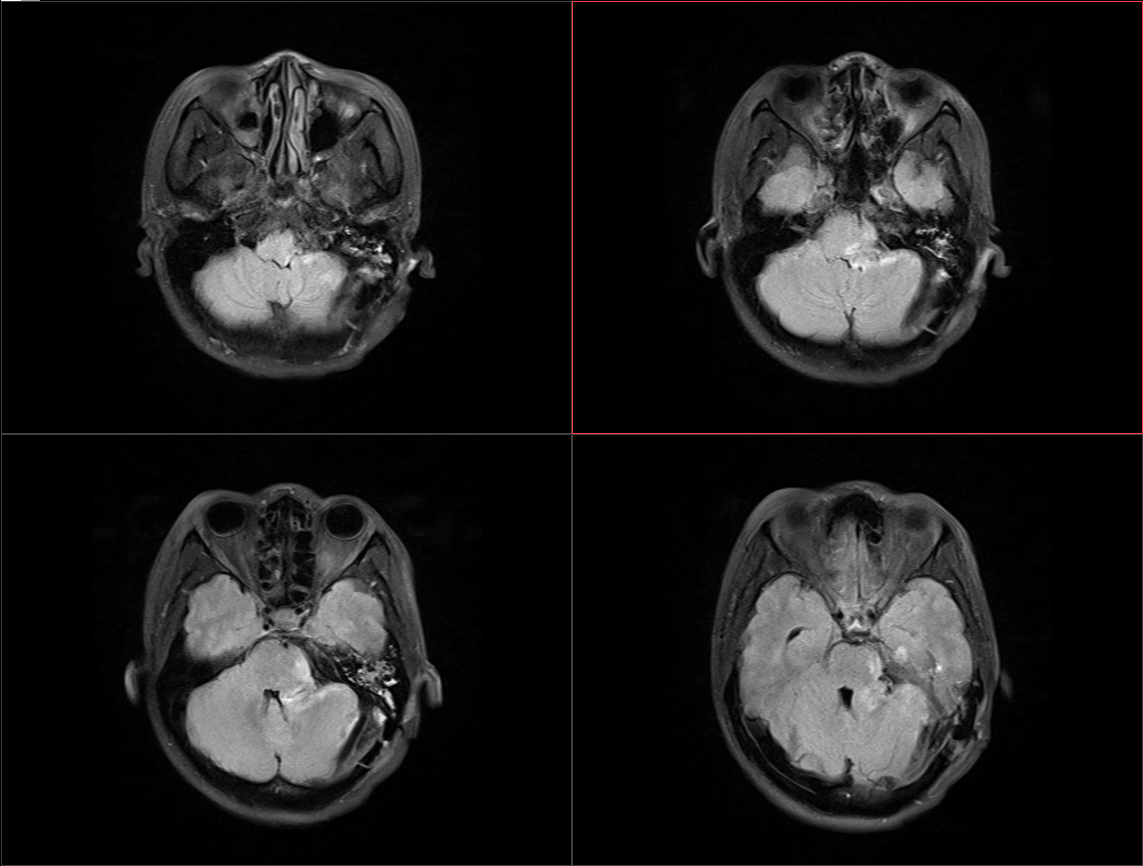

患者于入院前半年无明显诱因出现头痛、头晕,较剧烈,可耐受,无恶心、呕吐,无意识丧失,口服“止痛药(具体药名、剂量不详)”后症状稍缓解,入院前1周上述症状较前加重,患者前往当地医院就诊,行头颅MR示:1.左侧桥小脑角区占位,结合平扫及增强,现多考虑:皮样或表皮样囊肿。2。幕上梗阻性脑积水、脑室轻度积水。3.右侧上颌炎。现转至我院就诊。

术前影像: